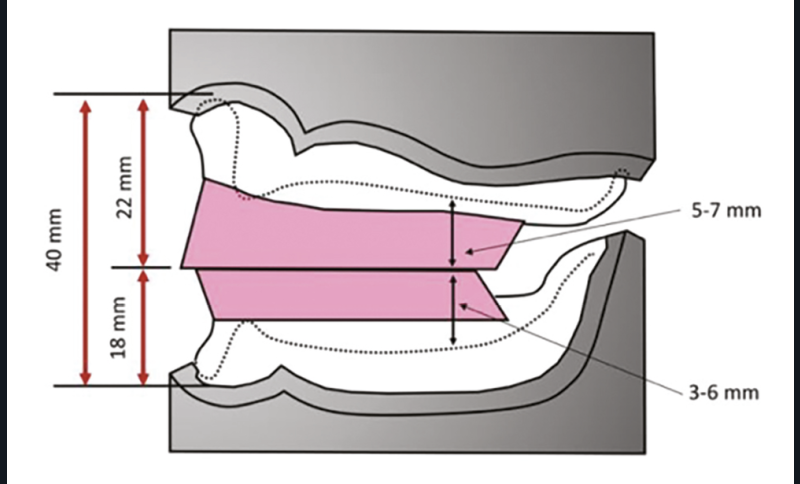

La DVO existe chez le denté : elle est stable, constante et reproductible, étant assurée par le calage occlusal. Chez l’édenté total, la DVO n’existe plus et on ne peut mesurer cliniquement que la dimension verticale de repos (DVR), correspondant en moyenne à la DVO à laquelle on soustrait la valeur de l’espace libre d’inocclusion (ELI), tel que DVO = DVR – ELI (fig. 1a-b).

Au maxillaire, la largeur du bourrelet est d’environ 6 à 8 mm en postérieur et doit suivre les aires de tolérance. En antérieur, sa largeur est de 4 mm et doit être monté en avant de la papille rétro-incisive de 6 mm environ afin de compenser la résorption osseuse. Il est incliné d’environ 10 à 15° vers l’avant. La hauteur mesurée du bord incisif au fond de sillon est d’environ 21 mm (fig. 5).

À la mandibule, le bourrelet suit la crête dans sa partie antérieure. Sa partie vestibulaire est concave et légèrement inclinée vers l’avant (sauf dans les cas de classe III où elle doit être dirigée vers l’arrière). La largeur du bourrelet est plus importante en postérieur (5 à 6 mm) qu’en antérieur (2 à 3 mm). La hauteur mesurée du bord incisif au fond de sillon est d’environ 18 mm. À l’arrière, le bourrelet doit s’arrêter aux deux-tiers du tubercule rétro-molaire (fig. 6).

Estimation de l’ELI (fig. 17)

La littérature rapporte des mesures comprises entre 0,3 et plus de 10 mm [11]. Toutefois, on peut proposer les valeurs suivantes :

• Chez les patients en classe I

ELI = 2 à 3 mm

• Chez les patients en classe II sévère

LI = 5 à 6 mm

• Chez les patients en classe III

ELI = 1 à 2 mm

L’ELI augmente avec l’âge.

En cas de doute, il est préférable de majorer l’estimation de l’ELI, car cela conduit à une sous-évaluation de la DVO qui est mieux tolérée.